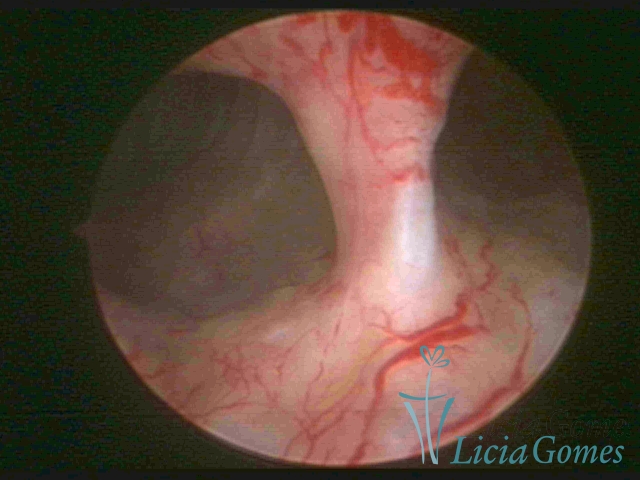

Unicornuate uterus

It presents a tubular cavity with an impaired intracavitary space, resembling the shape of a banana, whose the narrowest edge contains the tubal ostium. The endometrium is compatible with the menstrual cycle and the cervical canal is normal, in structure and trophism.